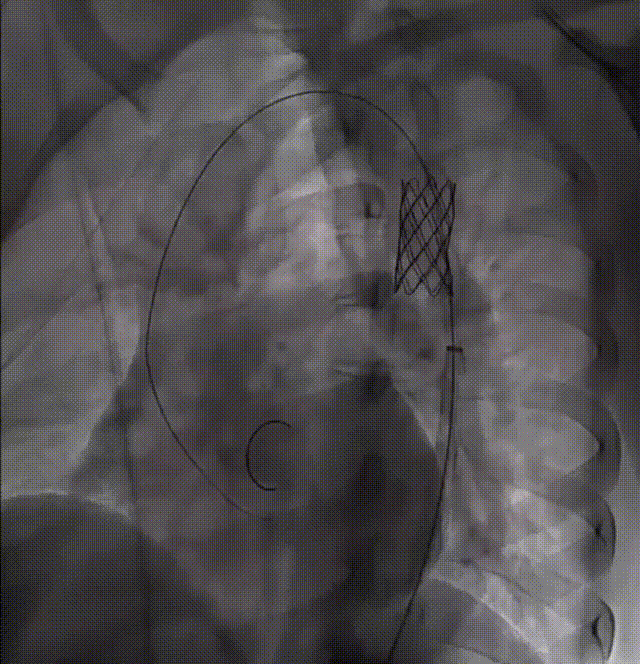

顺利完成CP支架组装后,经股动脉放置鞘管,成功将支架和球囊推送至血管缩窄段进行释放,血管造影结果提示预后效果理想。

术前、术后主动脉造影对比